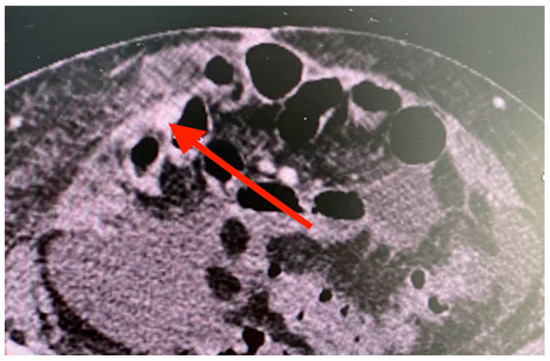

2. Case Presentation